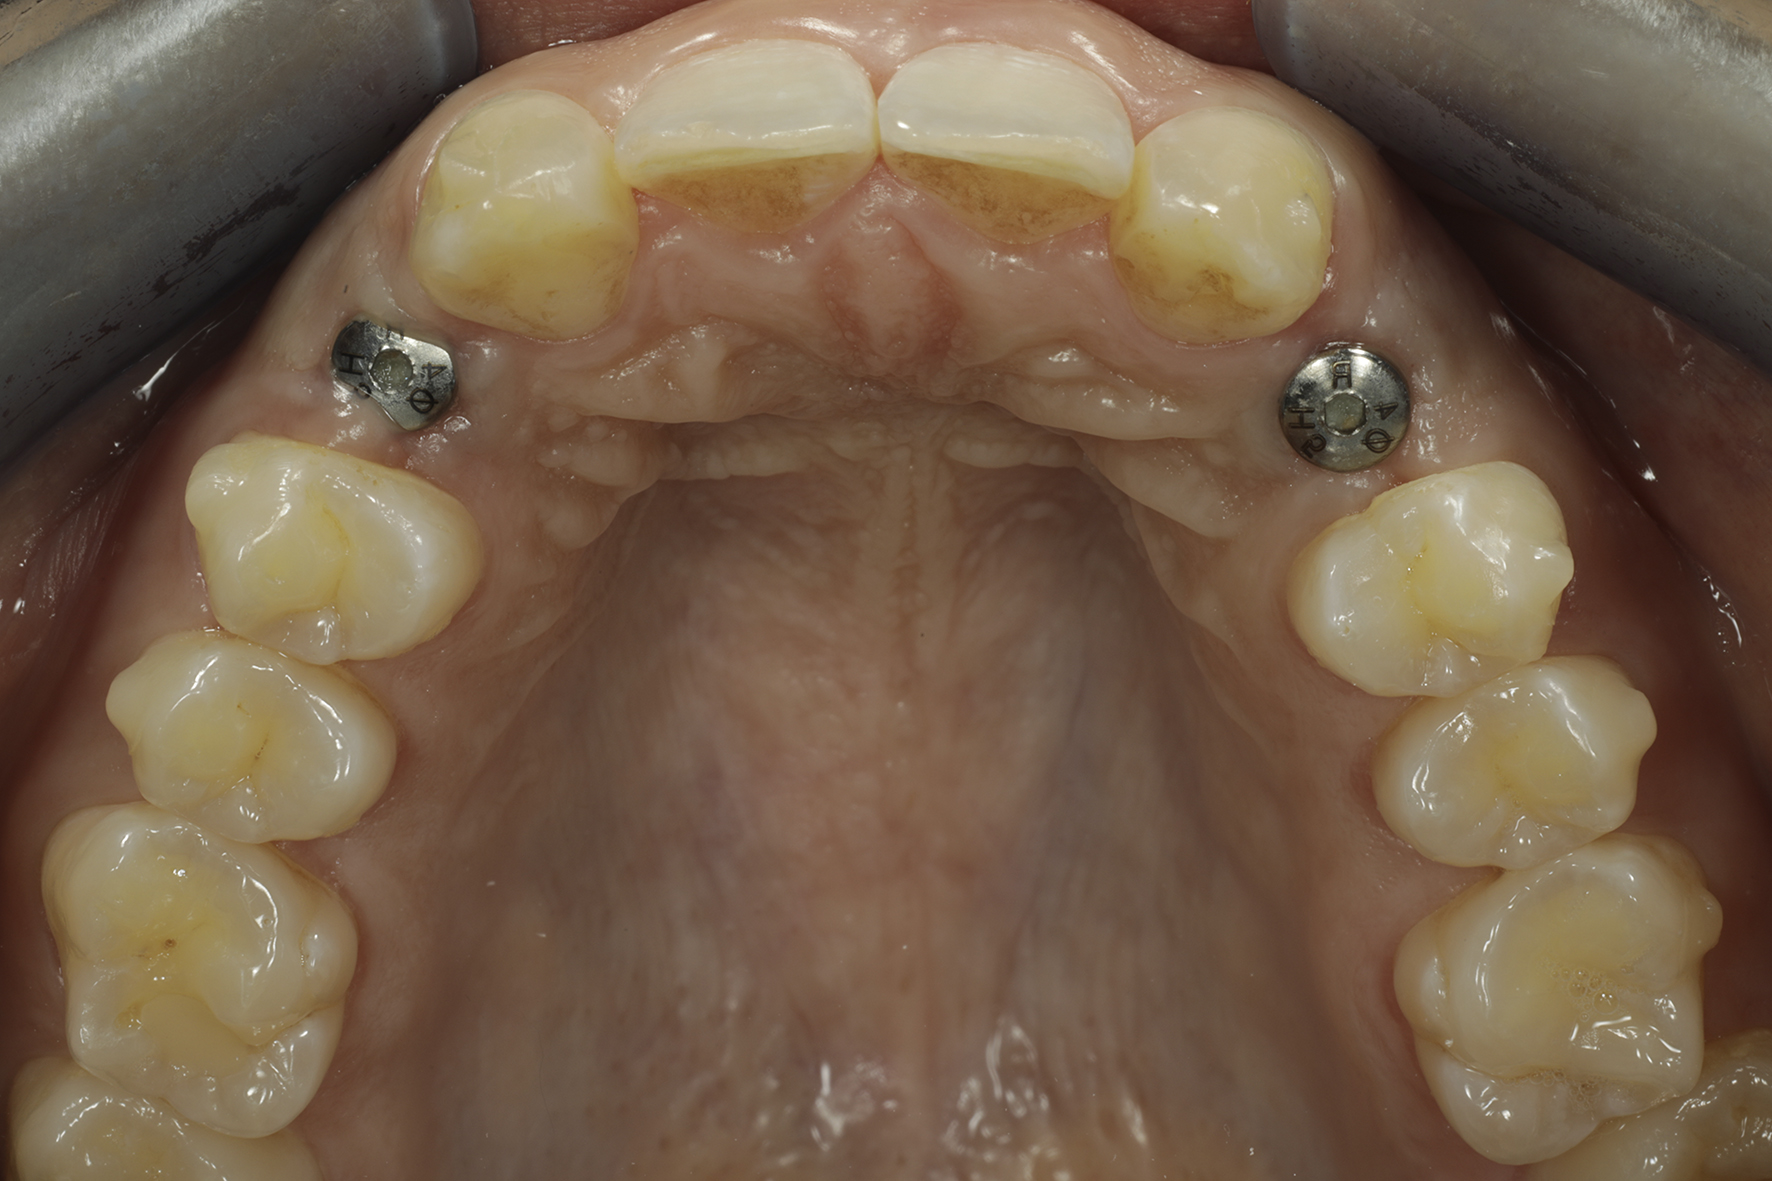

Näkymä okklusaalipeilin kautta nähtynä.

Implantit paikoillaan 1/3

Implantit paikoillaan 2/3

Implantit paikoillaan 3/3